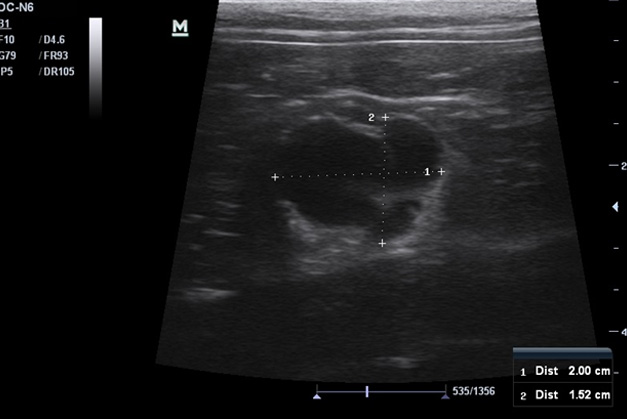

В сентябре 2018 года на плановый осмотр обратилась владелица кота Бони, возраст 8 лет. Во время диспансеризации была проведена ультразвуковая диагностика брюшной полости, по результатам которой была обнаружена патологическая структура на левой почке размером 2,0*1,5 см. Был поставлен предварительный диагноз – киста почки.

Для подтверждения диагноза с согласия владельцев была проведена пункция образования с аспирацией (откачиванием) жидкости под контролем УЗИ, под общей анестезией. После аспирации УЗ-картина левой почки соответствует норме. Аспирированная жидкость была отправлена в лабораторию на цитологическое исследование. По результатам цитологического исследования образование было идентифицировано как неинфицированная киста.